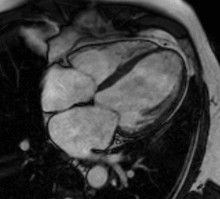

MRI sequences of a cardiac myxoma (a benign tumor)[1]

Cardiac magnetic resonance imaging (cardiac MRI, CMR), also known as cardiovascular MRI, is a magnetic resonance imaging (MRI) technology used for non-invasive assessment of the function and structure of the cardiovascular system.[2] Conditions in which it is performed include congenital heart disease, cardiomyopathies and valvular heart disease, diseases of the aorta such as dissection, aneurysm and coarctation, coronary heart disease. It can also be used to look at pulmonary veins.[3] Patient information may be found here.